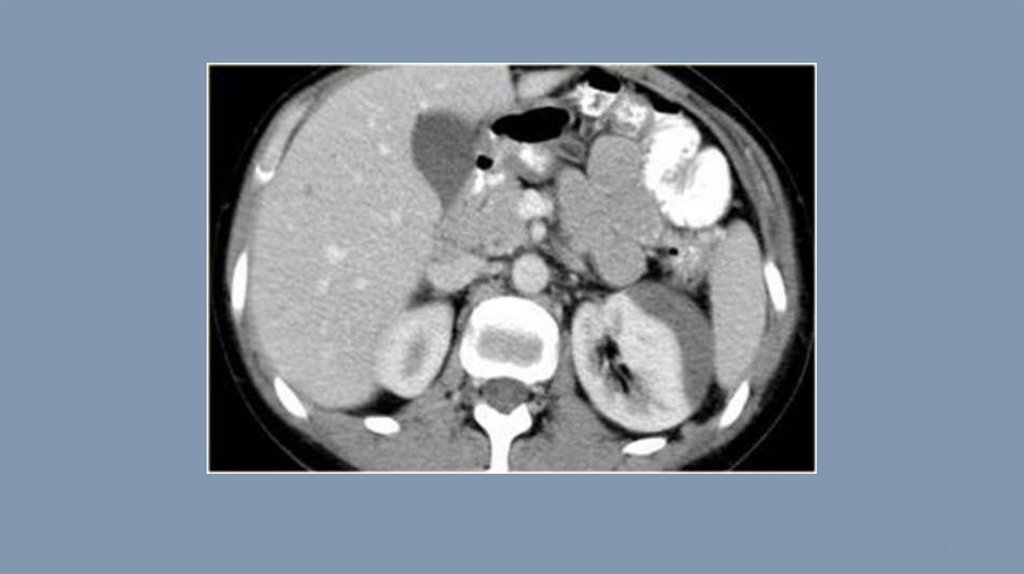

Компьютерная томография. Тест 14